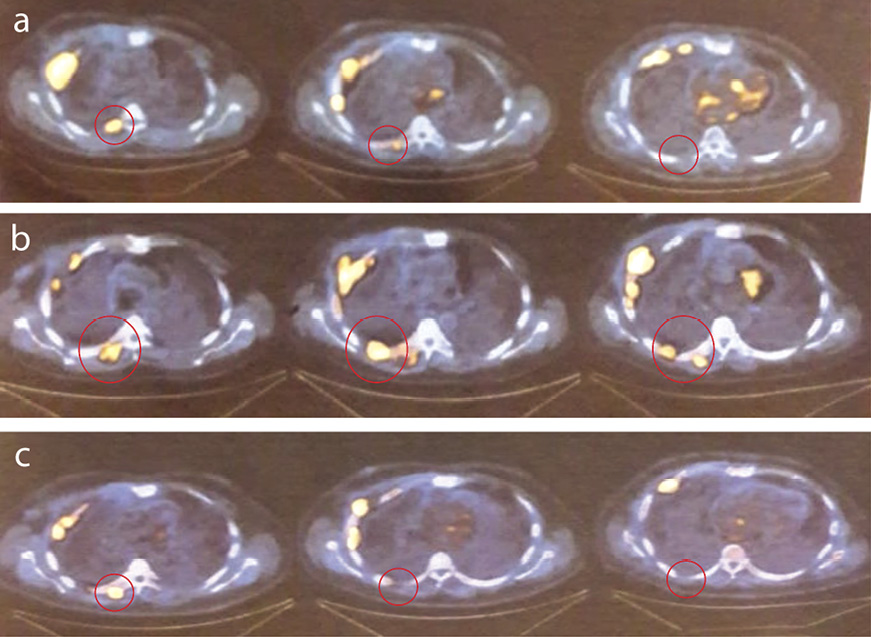

С учетом предшествующей положительной динамики после начала иммунотерапии (улучшение самочувствия, исчезновение В-симптомов) ситуация трактована как псевдопрогрессирование. Ухудшение после 8-го цикла ниволумаба объяснено сдавлением спинного мозга, увеличившимся на фоне псевдопрогрессирования мягкотканым компонентом. Гипотеза об имевшем месте псевдопрогрессировании оказалась верной. На фоне продолжения иммунотерапии пациент отметил регресс неврологической симптоматики, увеличение объема движений и силы правой ноги, восстановление пассажа стула. Феномен псевдопрогрессирования у пациента подтвердил и ретроспективный анализ исследований ПЭТ/КТ (рис. 5).

Рис. 5. Динамика изменений ткани опухоли по данным ПЭТ/КТ: а – до начала иммунотерапии; b – в период псевдопрогрессирования и ухудшения состояния (появление неврологической симптоматики); c – после регресса неврологической симптоматики.

В дальнейшем на фоне продолжения иммунотерапии у пациента – полный ответ опухоли на лечение. Общее число циклов иммунотерапии ниволумабом составило 23 (закончены в декабре 2019 г.).